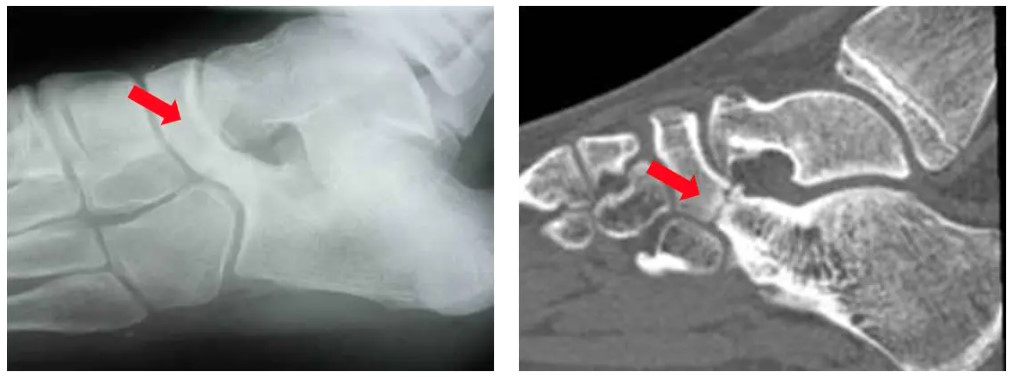

Bildgebende Diagnostik

Eine Röntgendiagnostik gibt dann häufig bereits erste Hinweise auf das Vorliegen einer Koalitio, die durch ein entsprechendes schnittbildgebendes Verfahren (MRT und-oder CT) gesichert werden. Kalkaneo-navikulare Koalitiones lassen sich im schrägen Röntgenbild gut darstellen. Talo-kalkaneare Koalitiones sind im konventionellen Röntgenbild nur durch indirekte Röntgenzeichen (Talar beak, C-Sign) erkennbar. Im CT und MRT ist dann die Diagnose zu bestätigen.